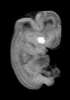

Carnegie Stage 19 (47 post-ovulatory days)

Most embryos at stage 19 are approximately 47-48 post-ovulatory days old and measure 17-20 mm in length. Distinguishing criteria for this stage include straightening of the trunk, the limbs extend nearly directly forward, toe rays are prominent, but interdigital notches have not yet appeared in the foot.

MRI Slice Selector

Mouse: click on a line below to select a view

Finger: tap a line below with a very light touch